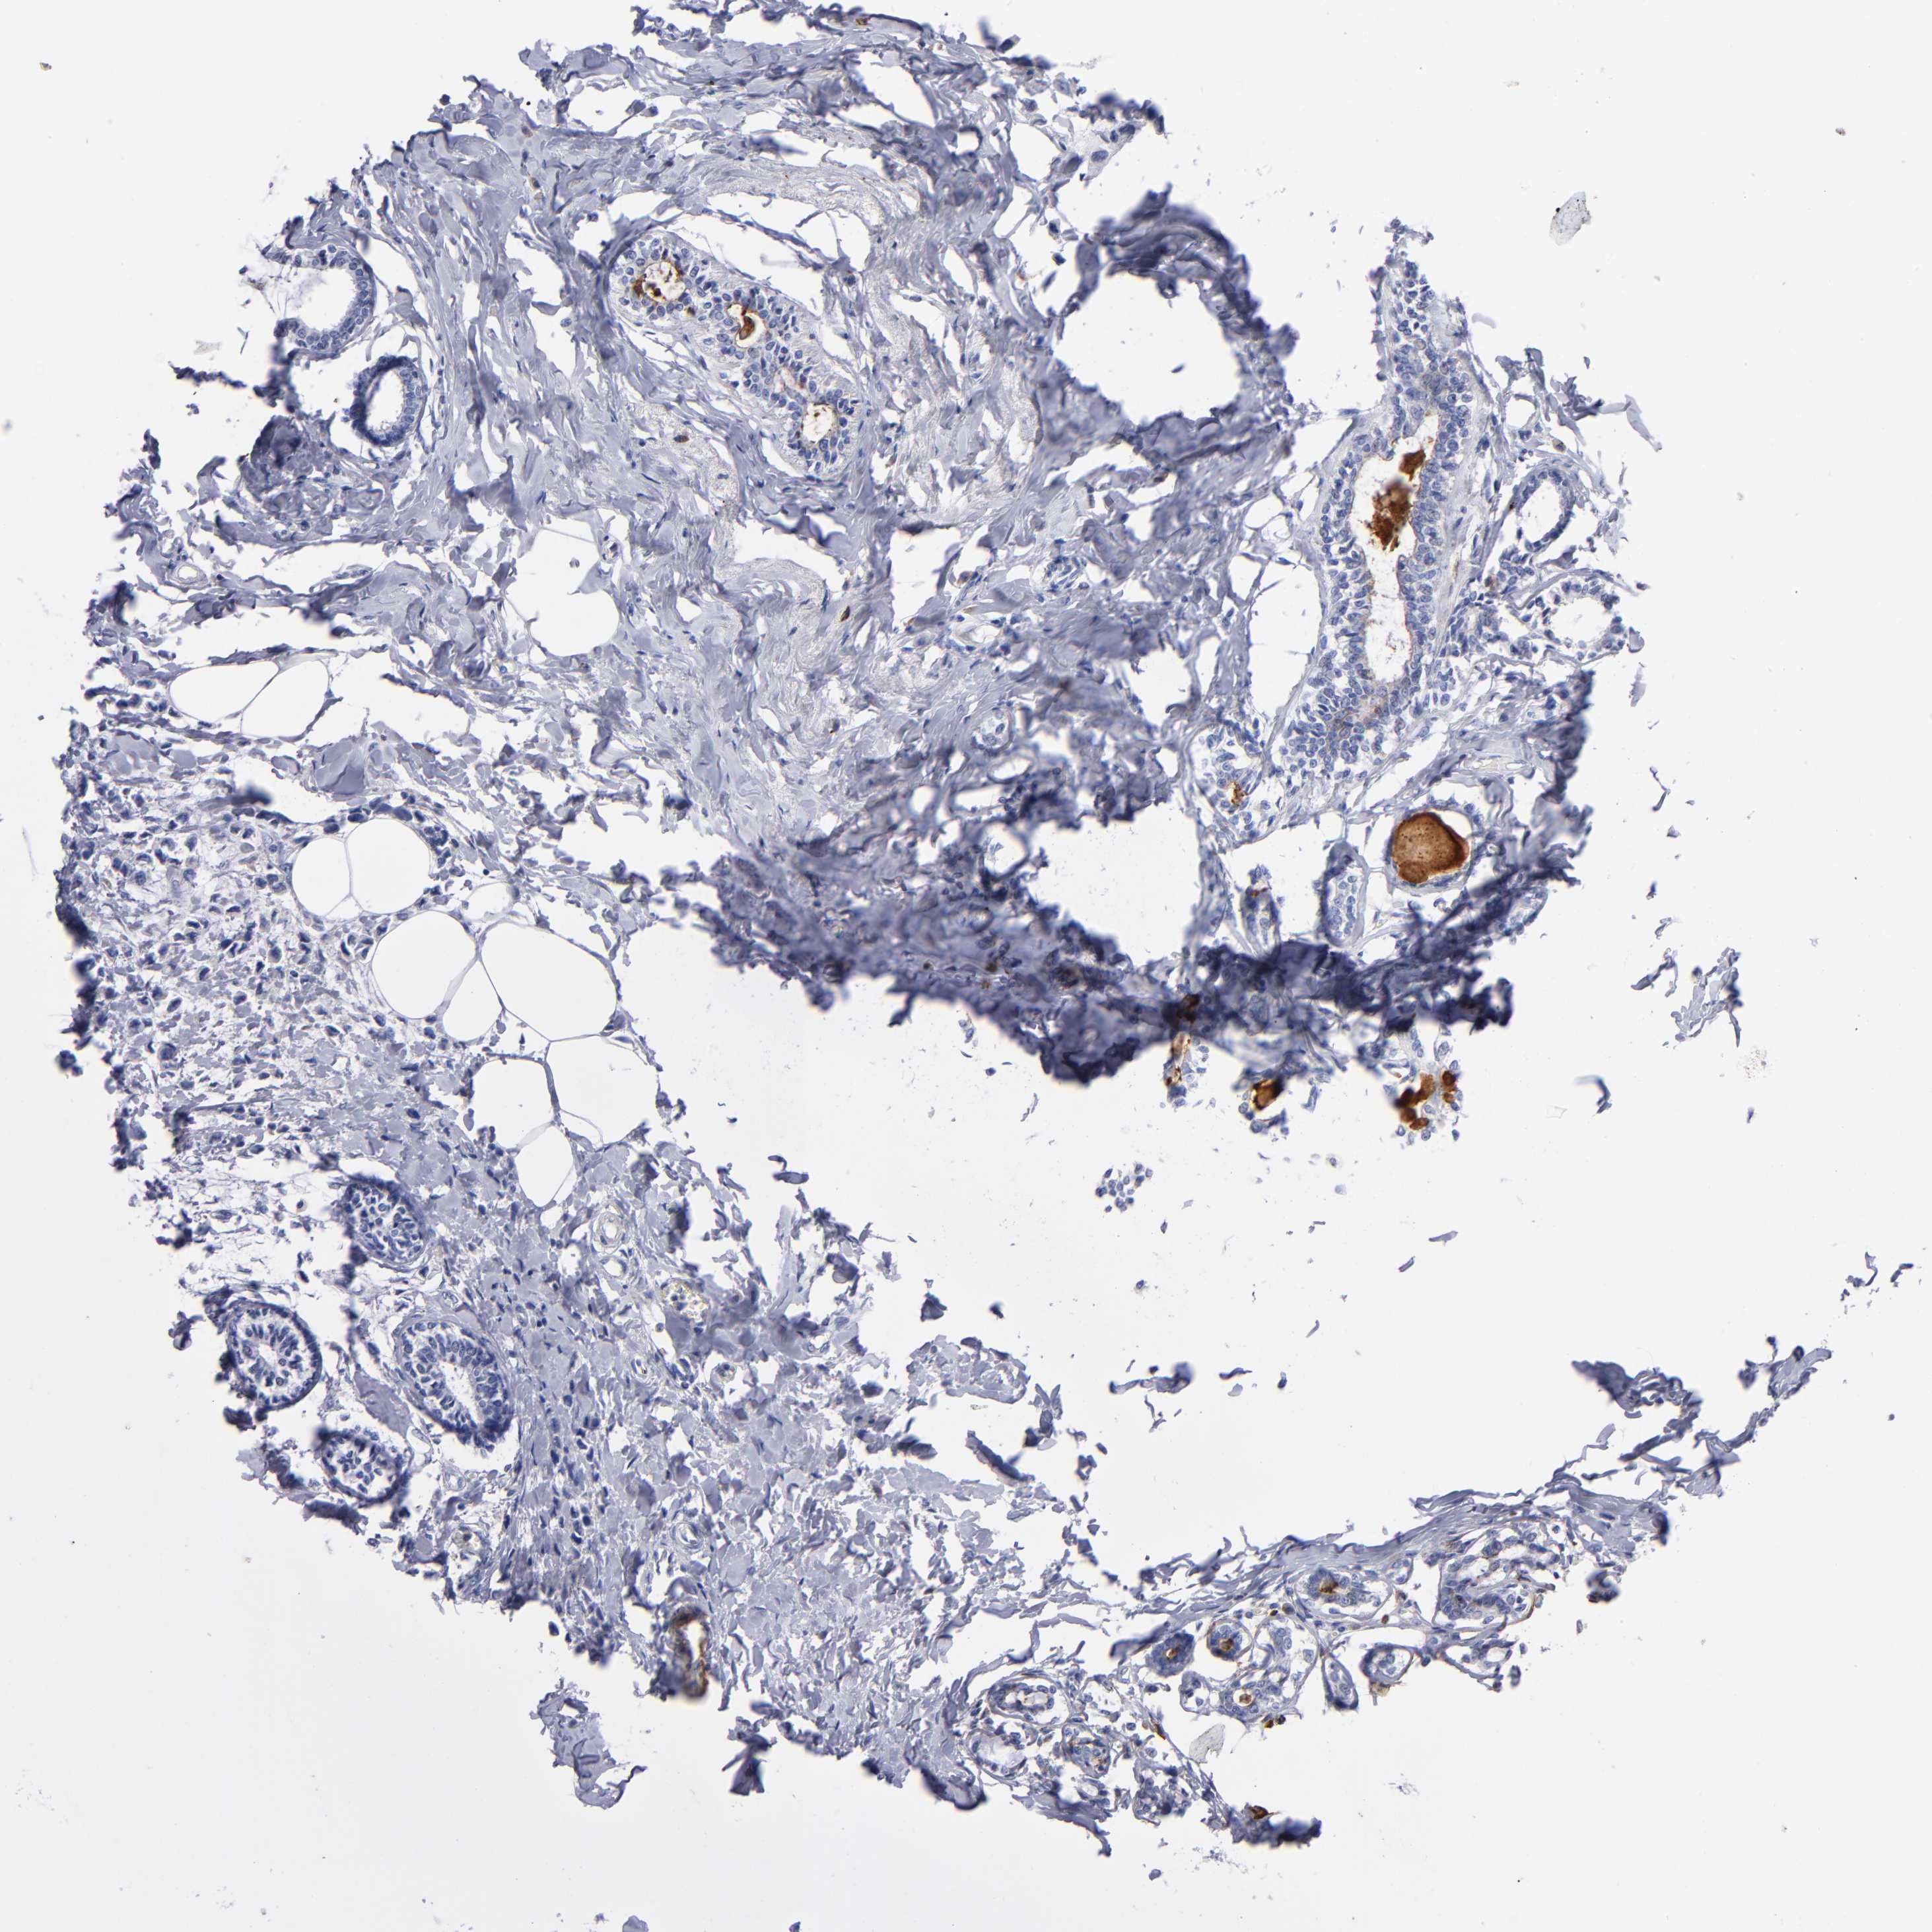

CANCER BREAST CANCER Show tissue menu

BRCA TCGA BRCA VALIDATION PROTEIN EXPRESSION